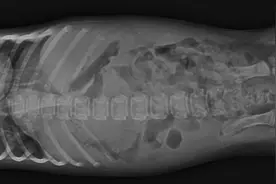

现在很多人都喜欢在家里饲养狗狗,狗狗确实能给我们的生活带来很多的乐趣。其中尤其是比熊犬有着一身洁白的被毛,体型娇小可爱,性格活泼伶俐,深得很多爱狗人士的喜欢。但是在比熊犬的饲养过程中比熊会遇到很多问题,其中尤其肺炎是比较麻烦的一种,那么引起比熊得肺炎的原因都有哪些呢?